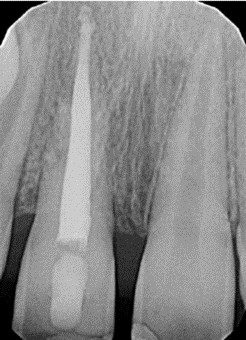

Na kontrolne badanie do lekarza stomatologa zgłosił się pacjent, który przed trzema laty przebył uraz siekacza górnego przyśrodkowego po stronie prawej. W wywiadzie pacjent nie podaje żadnych dolegliwości. W badaniu klinicznym lekarz stwierdza brak ruchomości zęba oraz metaliczny dźwięk na opukiwanie. Kontrolne zdjęcie rtg badanego zęba po leczeniu endodontycznym przedstawiono poniżej. Na podstawie zgromadzonych danych oraz rtg wskaż jakiego rodzaju urazu doznał pacjent: